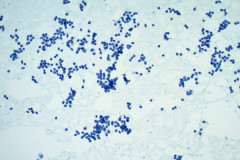

Cytology:

Aspirates of MTC are moderately cellular, showing a single cell pattern with occasional clustering and small aggregates. Cytologically, tumor cells can appear plasmacytoid, polygonal, or with spindle cells. Cells are uniform in size, but rare large pleomorphic cells may be present. The chromatin shows a coarse, granular, neuroendocrine pattern with inconspicuous nucleoli. Intranuclear inclusions may be seen, and nuclear grooves are rare. The cytoplasm is granular, and the amount is variable and rarely scant. Cytoplasmic dendritic processes may also be seen. Amyloid may be present in the background, although it can be identical to colloid in Papanicolaou-stained specimens. Variants of MTC include a follicular variant, papillary variant, small cell variant, giant cell variant, and a clear cell variant7. Cell blocks of MTC typically stain positive for calcitonin, CEA, TTF1, synaptophysin, and chromogranin, and are negative for thyroglobulin and PAX-88,9.

The tumor cells of this case presentation posed a diagnostic challenge due to their divergence from the typical cytological appearance of MTC. The majority of tumor cells had scant cytoplasm, including cells that resembled naked nuclei and cells with a plasmacytoid appearance. A diagnosis of MTC was rendered in conjunction with the patient’s elevated calcitonin level, history of MTC and MEN2, and comparison to the patient’s previous two MTC diagnoses.